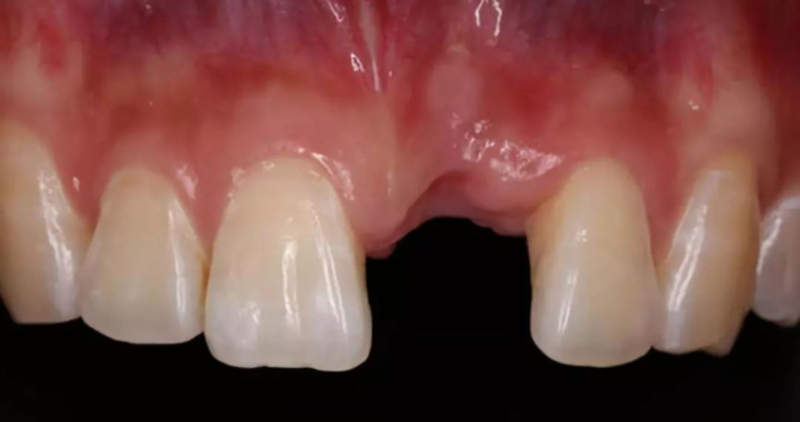

*前牙美學區(qū)種植,病人為正畸治療后,對美學要求高

*早期種植病例,頰側(cè)組織凹陷,肉眼可見骨缺損,需要種植同期GBR

*CBCT顯示骨缺損嚴重,種植窩洞制備困難,種植體很難獲得初期穩(wěn)定性